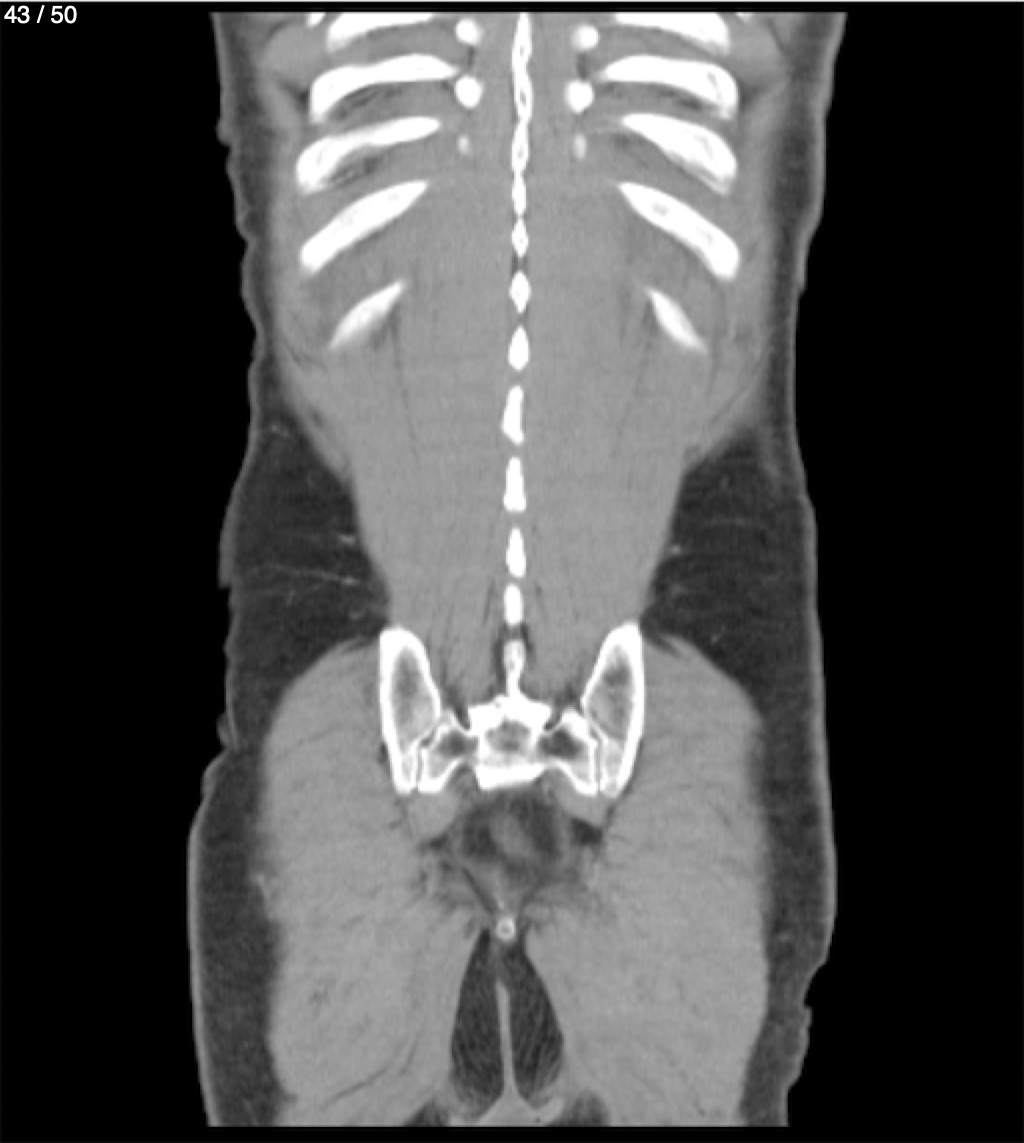

Alonso Victorio Ruiz 62A - T.C Abdomen Syc